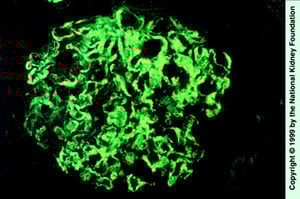

Deposizione sparsa di IgG nel mesangio e nelle anse capillari (colorazione con immunofluorescenza con anti-IgG, ×400).

Imagine fornita da Agnes Fogo, MD, and the American Journal of Kidney Diseases' Atlas of Renal Pathology (vedi www.ajkd.org).